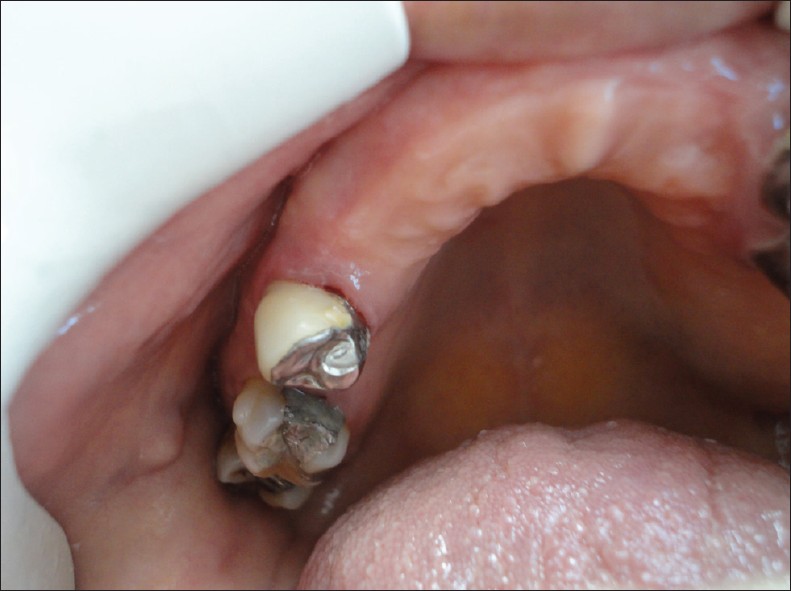

Management of dental - orthopedic problems in down syndrome

Sertac Aksakalli, Zehra Ileri

Down Syndrome (DS) is one the most prevalent genetic disorder. This genetic disorder has physical and mental features including musculoskeletal (e.g. incorrect swallowing pattern), nervous (e.g. anxiety), and dental problems. Maintaining oral health is very important for these kinds of patients. Oral health or dental problems related to DS are localized or generalized periodontitis, mandibular prognatisma, underdeveloped maxilla, caries lesions, delayed eruptions, and oligodontia. Because of dental-oral part is the first part of the digestive system, there is need for orthodontic treatment maintaining better occlusion and mastication. In this case report, orthopedic, orthodontic, periodontal, prosthetic, and conservative dental treatments of a DS patient were presented. These kinds of patients should not be excluded from the dentistry patient population.